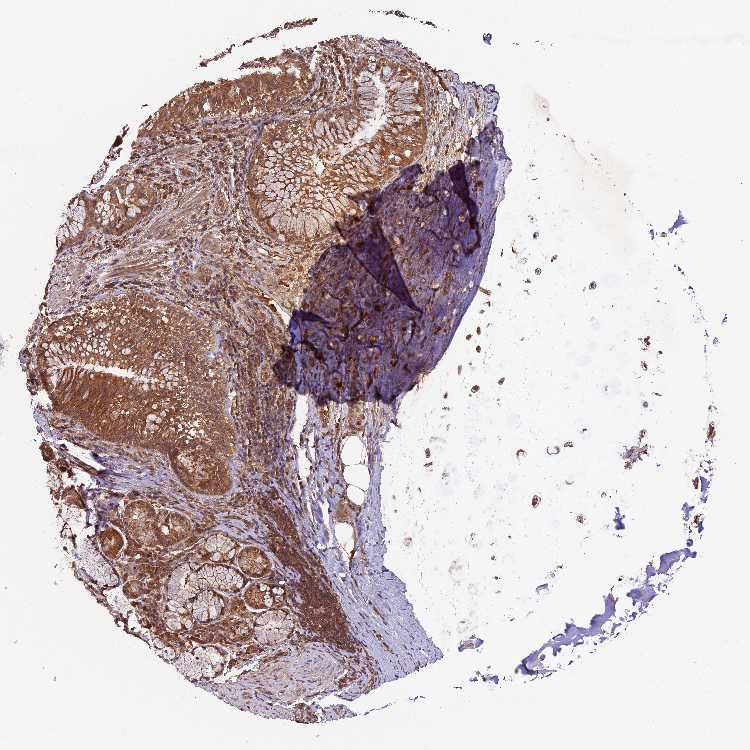

SOFT TISSUE 1 - Antibody stainingi

Antibody staining in the annotated cell types in the current human tissue is reported as not detected, low, medium, or high, based on conventional immunohistochemistry profiling in selected tissues. This score is based on the combination of the staining intensity and fraction of stained cells.

Each image is clickable and will lead to virtual microscopy that enables deeper exploration of all samples and also displays staining intensity scores, fraction scores and subcellular localization as well as patient and tissue information for each sample.

Antibody HPA042708Antibody HPA043505

Chondrocytes HighNot detected

Fibroblasts LowNot detected

Peripheral nerve MediumNot detected